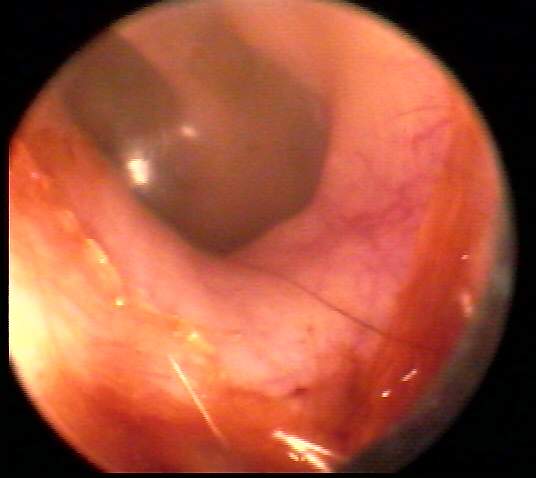

O:Cerumen entirely absent or present in a small amount, insufficient to limit audiological access to the ear in any way. Tympanic membrane may be fully visualized, including the annulus. Removal not indicated. EXAMPLES: 0/A(18k) | 0/B(17k) | 0/C(18k)